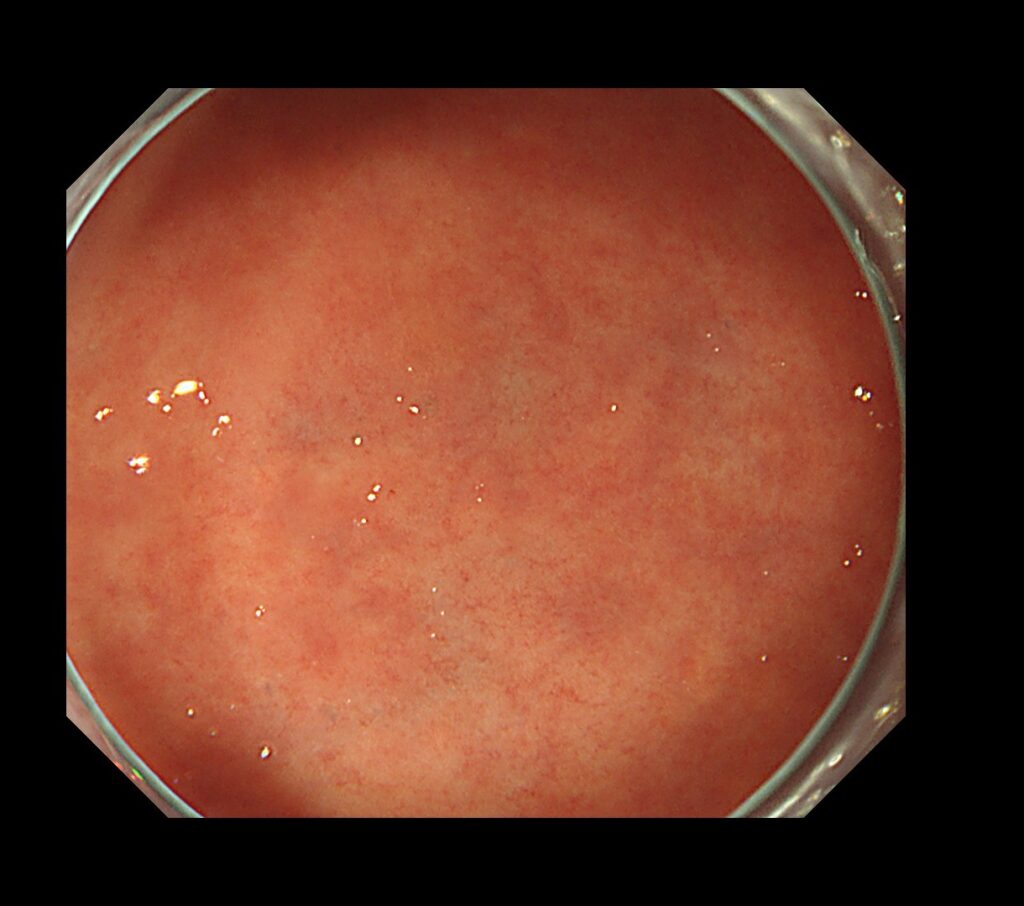

通常光では、全く病変を指摘できない状態と判断。

ピロリ菌除菌後ということもあり、病変は忍者のように隠れています。

①通常光での病変を発見しにくい時代に到来(平らな腫瘍が多い)

繰り返しますが、ピロリ除菌後の時代は、通常の観察では見逃される病変が多数存在します。